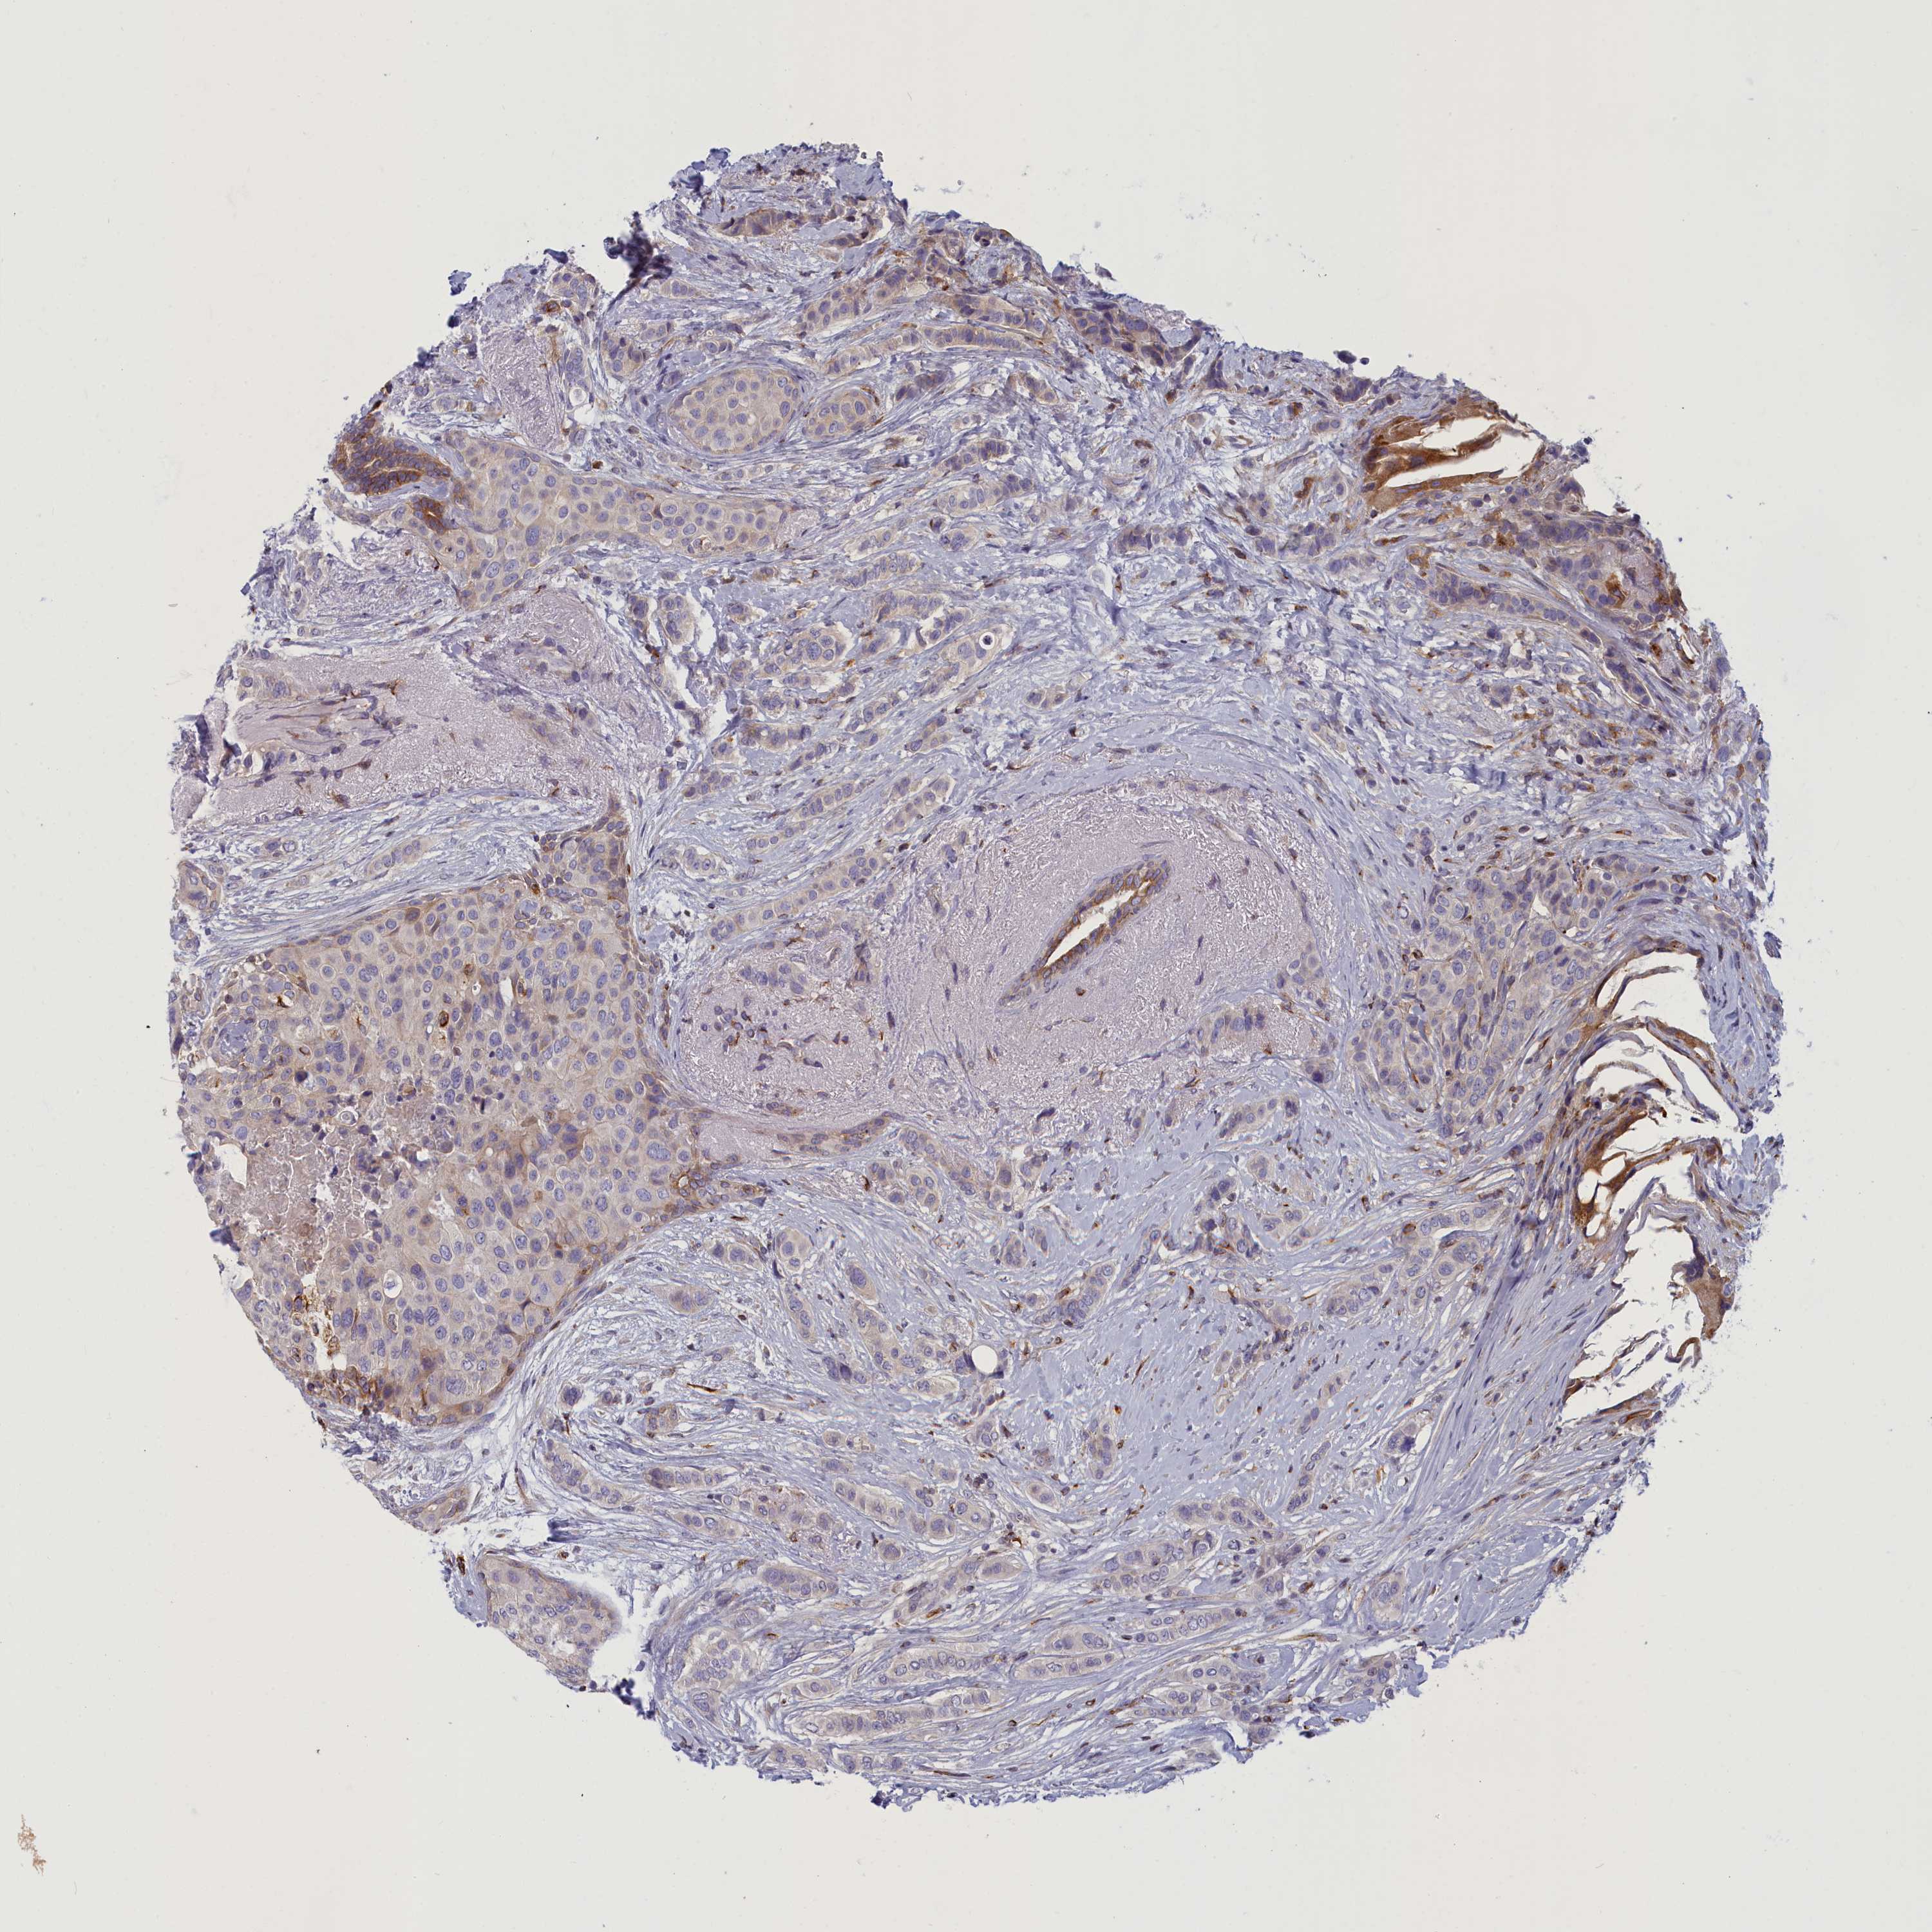

CANCER BREAST CANCER Show tissue menu

BRCA TCGA BRCA VALIDATION PROTEIN EXPRESSION